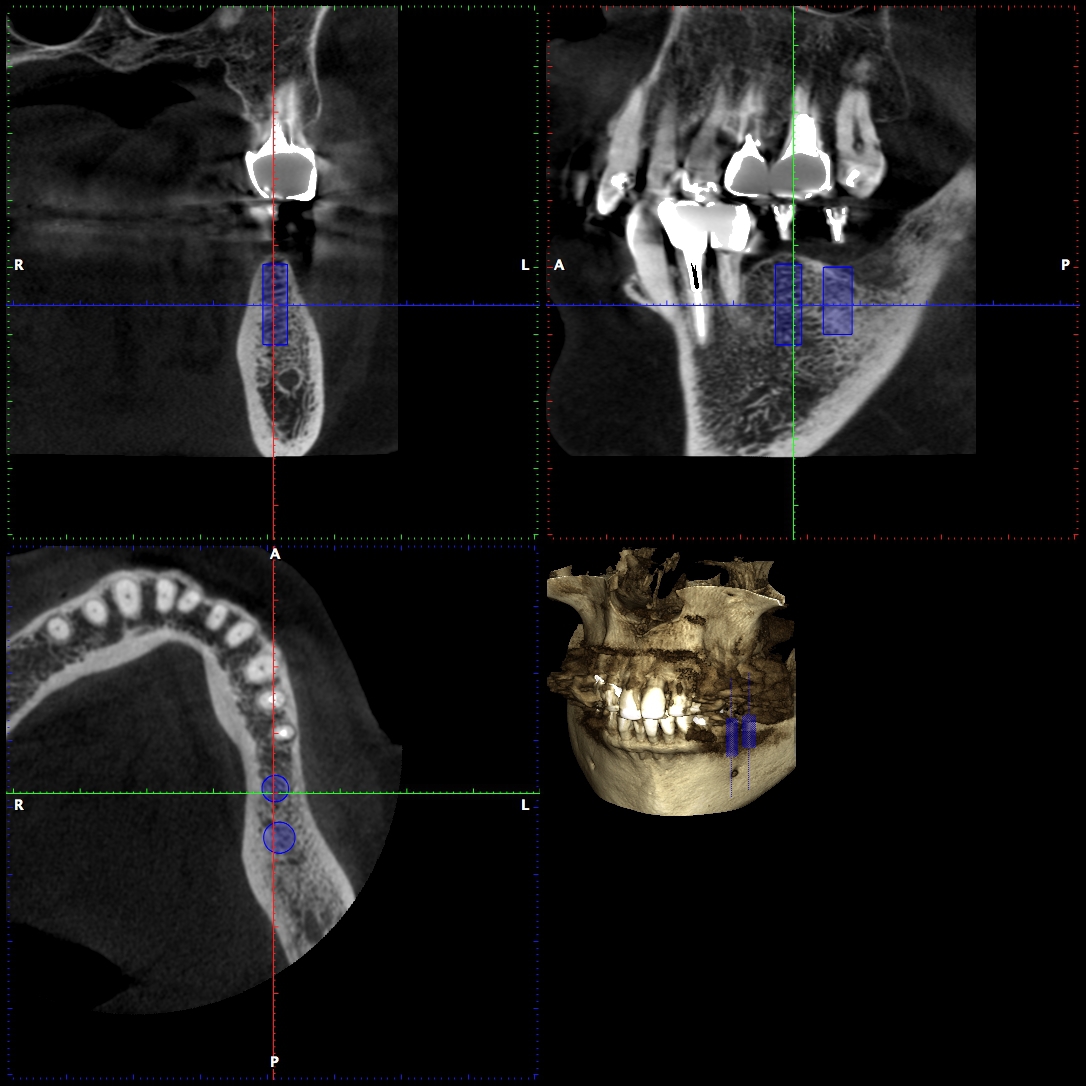

インプラントとCT

インプラント治療に必要なことは、顎の骨の状態(質や厚み、高さ、形態など)を把握することです。CT画像からは顎の骨の内部構造(骨の高さ、厚み、神経・血管の位置)を立体的に確認することができ、より正確な診断が可能となりました。術前のシュミレーションを行うことで、より安全・確実にインプラントを埋入することができます。

オリエント歯科では、インプラント手術前に必ずCT撮影を行っております。